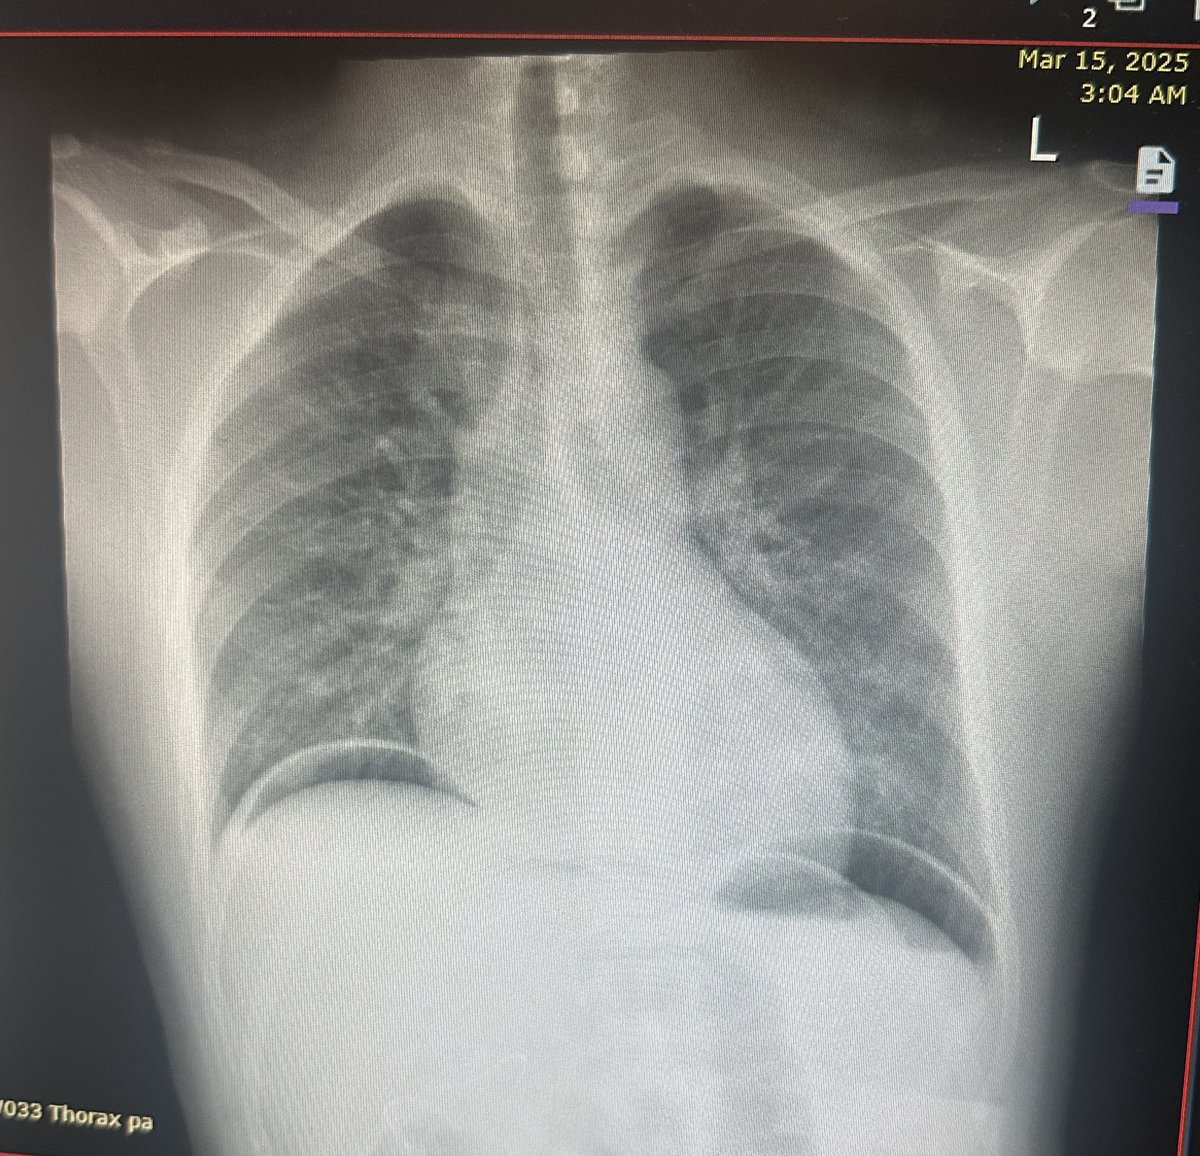

#Tension_pneumothorax on the right side in a newborn: #Findings 1.Deep sulcus sign 2.Mediastinal shift to the left - opposite side (heart, trachea, and esophagus) 3.Total lung collapse on the right (same) side #Tension_Pneumothorax_in_Newborns •Tension

hemo_shk's tweet image. #Tension_pneumothorax on the right side in a newborn:

#Findings

1.Deep sulcus sign

2.Mediastinal shift to the left - opposite side (heart, trachea, and esophagus)

3.Total lung collapse on the right (same) side

#Tension_Pneumothorax_in_Newborns